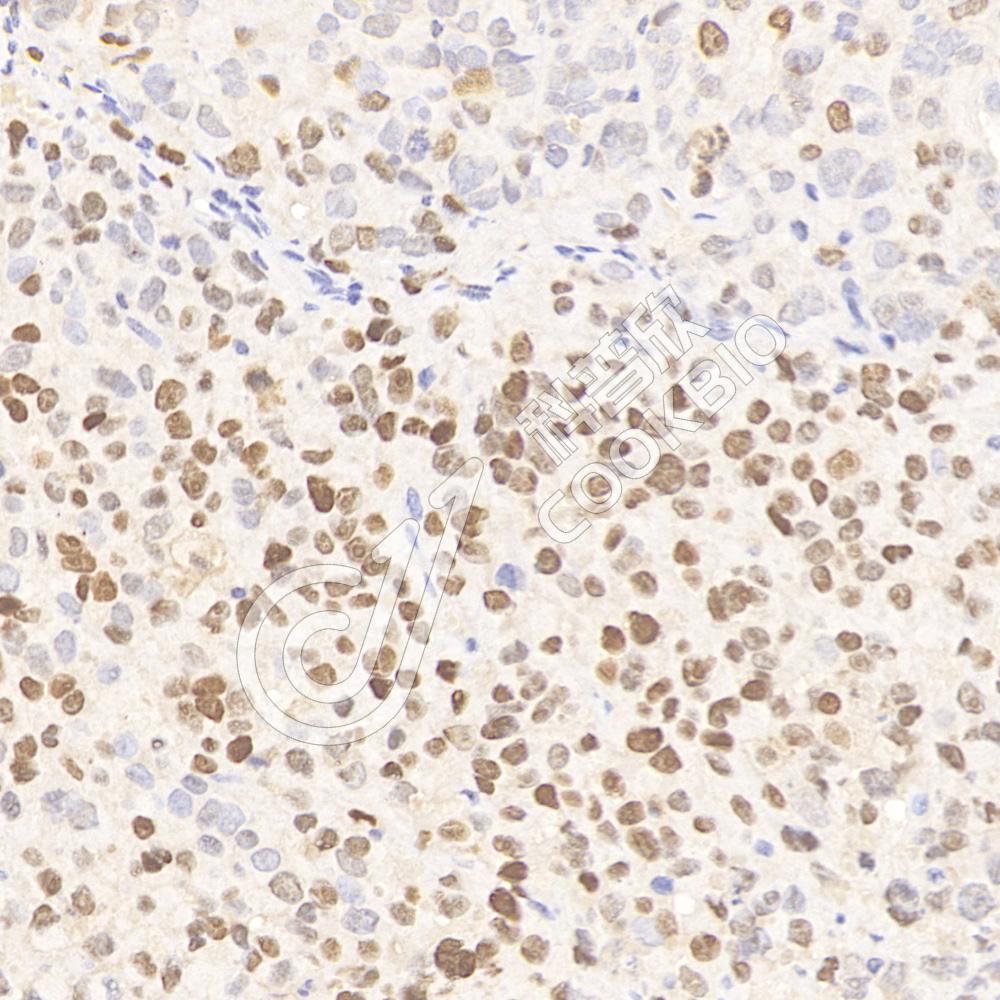

IHC检测p53蛋白(货号 K134878).

样品: 人卵巢癌, 4%多聚甲醛 (货号KSG1101) 固定12-24小时.

抗原修复: 柠檬酸抗原修复液(干粉, pH 6.0) (KSG1201), 98℃, 20分钟.

—抗: 1: 1800稀释, 4℃ 孵育过夜.

二抗: S-vision免疫组化多聚二抗(山羊抗兔),即用型 (货号KB3906), 室温孵育20分钟.